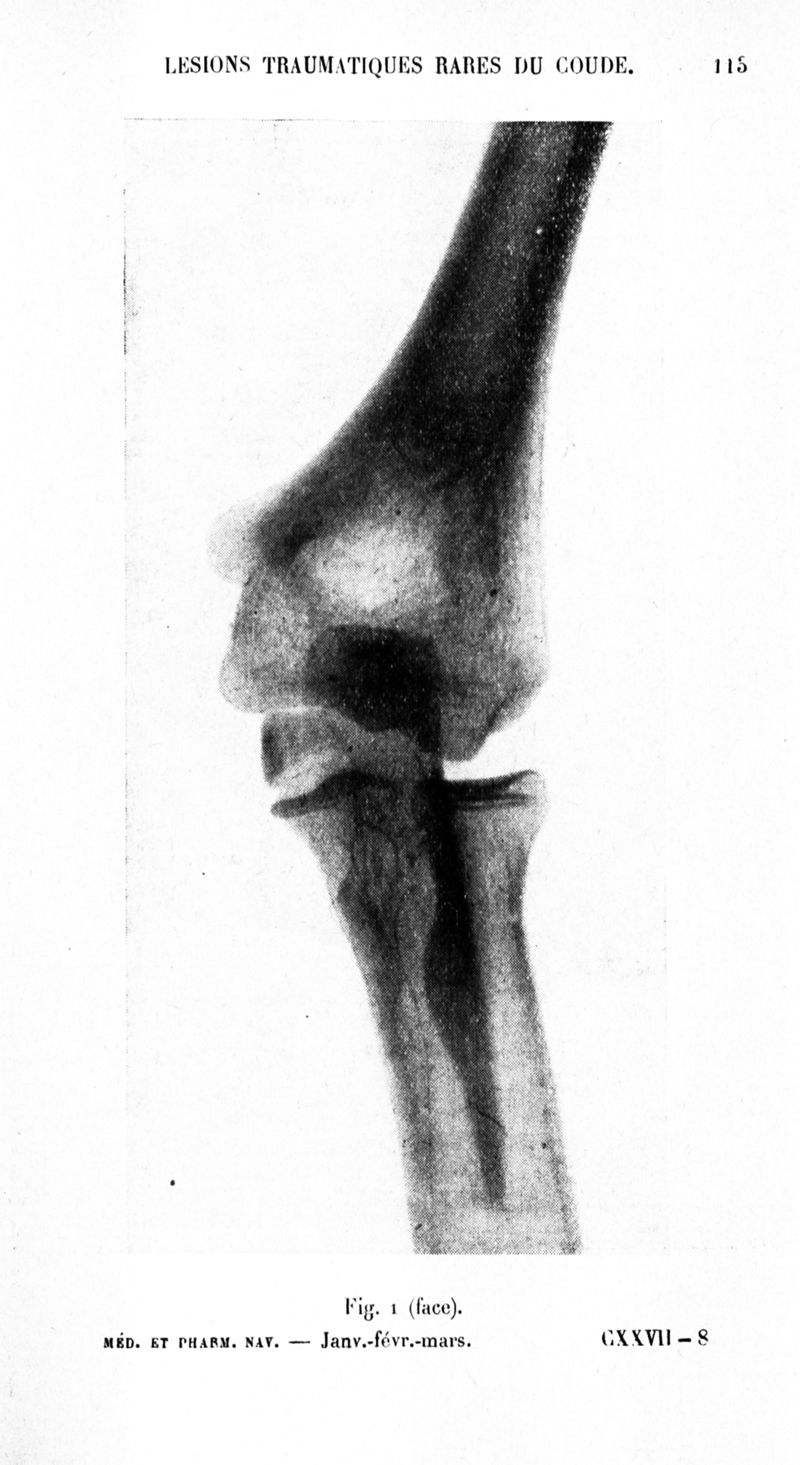

Archives de médecine et pharmacie navales

1937, n° 127. - Paris : Imprimerie nationale, 1937.